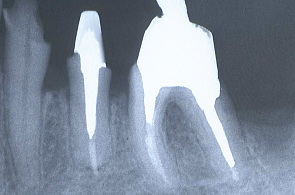

製作した鋳型を口腔内の歯牙に入れ、レントゲンを撮り適合を検査する。

下顎の歯牙にも同じようなものを作りレントゲンで根っこを検査した。